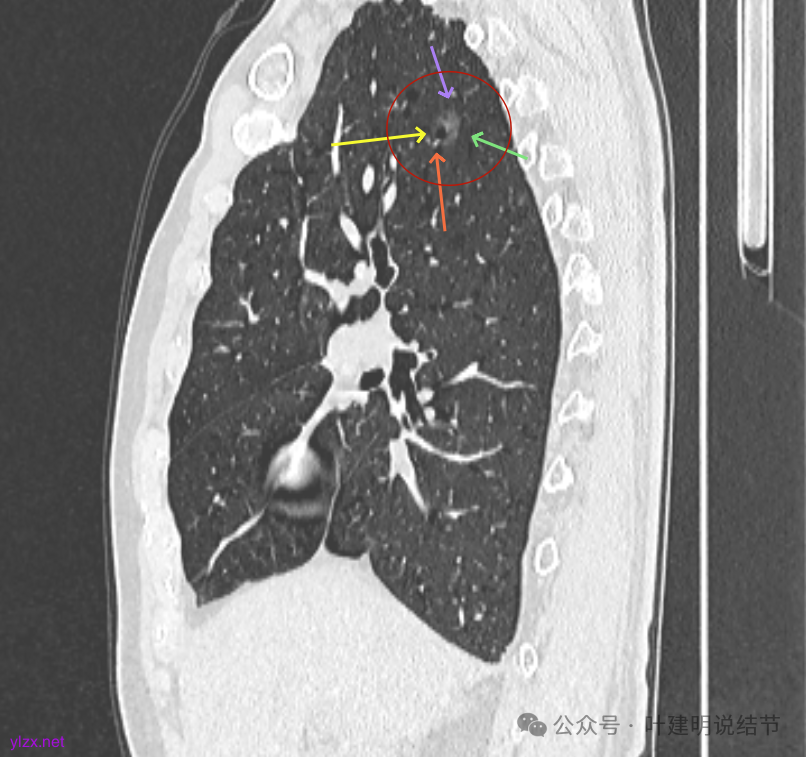

最后看2025年3月的连续层面的影像细节:

右上病灶淡磨密度,有空泡征,整体轮廓较清。

瘤肺边界清楚,空泡征明显。

表面不平,没有实性成分。灶内空泡有些像蜂窝状。

病灶边上有小血管走行,整体轮廓清,没有明显实性成分。

右上病灶淡而纯主要原因,空泡征明显。

左上病灶淡而纯,有微小血管进入。

右上淡磨,轮廓清,空泡明显。

左上的小而局部有细支气管扩张的样子,部分边缘显毛糙,有细毛刺样征。

右上叶病灶有血管贴边,轮廓清;

左上病灶纯磨,轮廓清。

矢状位见右上病灶也是纯磨,灶内的血管可见,表面部分有细毛刺,整体轮廓与边界清楚。

左上病灶矢状位见也是纯的,没有实性成分。